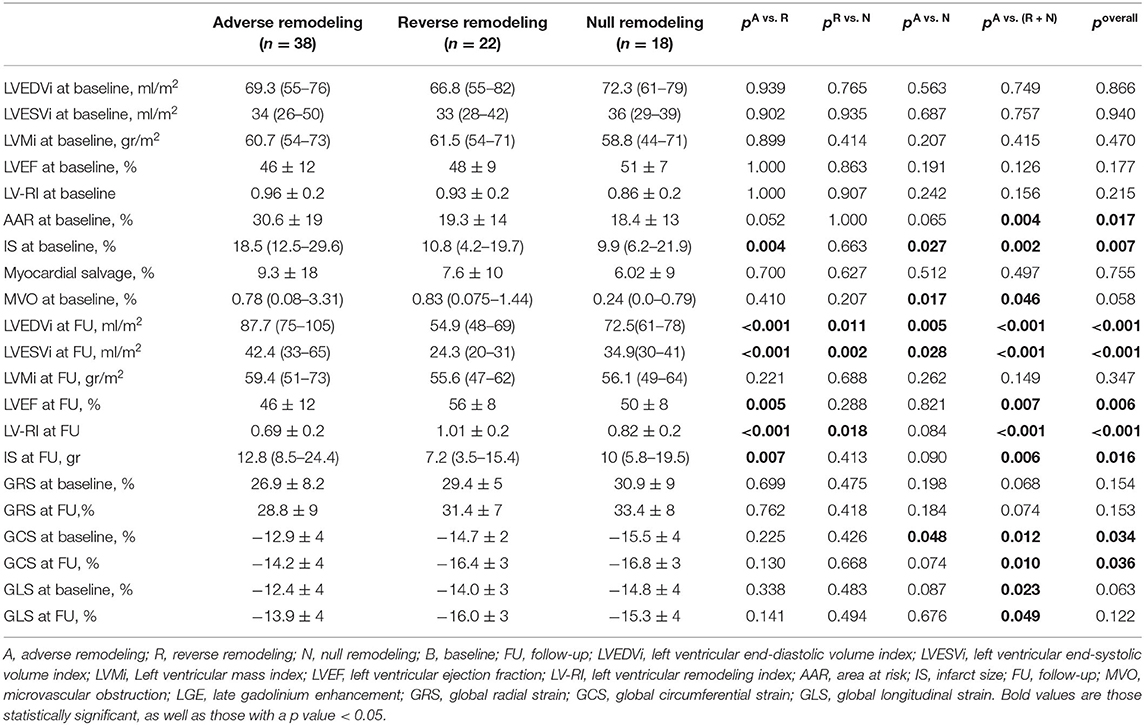

From 2010 to 2019, a total of 1,285 STEMI patients underwent pPCI in Policlinico Umberto I Hospital, of which ~15% had CMR performed and 78 were recruited as reported in the flow chart (Figure 1). According to our internal procedures, when allowed by the clinical condition of the patient, the availability of the scanner/staff, and in the absence of contraindications, CMR was performed in reperfused STEMI patients for the assessment of post-infarction myocardial injury during the acute phase and to detect complications at short and long term follow up. Among the study population of enrolled STEMI patients, 38 (49%) showed adverse, 22 (28%) reverse, and 18 (23%) null LV remodeling, assessed by paired CMR exams (baseline and FU-CMR). Demographic, clinical, angiographic, and pharmacological characteristics of the STEMI population according to the three groups are illustrated in Table 1. No differences in demographic data, cardiovascular risk factors, angiographic presentation, or laboratory findings were found. Agreement in strain measurements was excellent with ICC between 0.922 and 0.943 (p < 0.001, Supplementary Material) and p > 0.43 (range 0.43–0.85) at Wilcoxon's test. Regarding pharmacological therapy, no differences were noted about beta-blocker, antidiabetics, statins, ACE-inhibitors, spironolactone, GbIIb-IIIa inhibitors, and clopidogrel use among the three LV remodeling categories, except for the pre-pPCI ASA administration. At the first CMR exam, patients with LV adverse remodeling showed higher AAR, IS, and MVO, if compared to the other two groups (Table 2). Meanwhile, at FU-CMR, the adverse remodeling group had lower LVEF, greater IS extent, and lower LV-RI. At CMR strain analysis, significantly worse GCS and GLS values at baseline and FU-CMRs in the adverse LV remodeling group, compared to the sum of the other two groups, were found (Figure 2, Table 2). After adjusting for age, sex, BMI by ANCOVA analysis, the only CMR derived parameters that reported a different statistical significance if compared with ANOVA analysis, according to the three remodeling groups, were baseline AAR, baseline MVO, FU IS, baseline GRS, and baseline GLS.

Table 1. Demographic, clinical, pharmacological, and angiographic characteristics according to LV remodeling groups.

CMR Parameters in Predicting LV Remodeling

In this study, we categorized the population using the three LV remodeling patterns based on Bulluck's definition (7), observing a similar percentage distribution (adverse remodeling 49 vs. 45%, reverse remodeling 28 vs. 29%, and null remodeling 19 vs. 23%). For CMR parameters, the adverse remodeling group showed greater AAR, IS, and MVO at baseline CMR and greater IS at FU-CMR, as already reported (7). Otherwise, no differences in IS and MVO between reverse and null remodeling groups were found in our study. Notably, there were no differences in salvage myocardium extent among the three groups. Although IS and MVO are known predictors of adverse remodeling (7), the relationship between them and myocardial recovery is still an open issue (6, 7). Moreover, at FU-CMR, the adverse remodeling group showed lower LVEF, LV-RI, and greater IS, as compared to the other two groups. Regarding FT-CMR strain analysis, the adverse remodeling group showed worse GCS and GLS values at baseline and FU-CMR (Figure 5), if compared to reverse and null remodeling categories as one. Various studies investigated the value of FT-CMR features in predicting adverse remodeling (11, 12, 22), using different cut-off values and follow-up periods. For the definition of adverse LV remodeling, we considered LVEDV and/or an LVESV delta change of 12%, which is lower than most reports, and 6 months for follow-up, longer if compared to other studies, mostly around 3/4 months. Thus, this issue may have induced a larger rate of adverse remodeling in our population (49%), as compared to other cohorts (17–24.4%) (11, 12, 22, 23). In the majority of studies, baseline GLS was the best predictor of adverse remodeling among all strain values (11, 22–24). In particular, Reindl et al. (22) reported significant differences in baseline strain values and infarct size/MVO percentage between no remodeling and remodeling groups, as observed in our cohort. Moreover, they showed that a GLS-value > −14% was the best independent predictor of 4 months LV adverse remodeling (LVEDV delta change of 10%) with an AUC of 0.610, which do not differ substantially from our GLS AUC value of 0.639 using LVEDV/LVESV delta change of 12%. In the retrospective study of Cha et al. (11), at ROC curve analysis (AUC: 0.756, 95% CI = 0.636–0.887, p < 0.001), the GLS cut-off of −12.84% resulted in high sensitivity (Se: 85%) and low specificity (Sp: 61%) in predicting adverse remodeling at 6 months (LVEDV delta change of 20%), whereas in our study the optimal cut-off was lower (GLS > −10.21%), with lower sensitivity (Se: 35%) and higher specificity (Sp: 90%), likely reflecting the different criteria in classifying the remodeling groups. Interestingly, in our study GCS was the strongest predictor of adverse remodeling among the baseline strain values, as already reported by other authors (12, 25, 26). Holmes et al. (12) found that GCS was a superior predictor of LV adverse remodeling at 3 months follow-up than MVO, GLS, and GRS, although they considered a cohort of both STEMI and non-STEMI patients (12), differently from our population of STEMI only. Similarly, Buss et al. demonstrated that GCS is useful in predicting preserved LV function at 6 months follow-up but they did not evaluate LV remodeling groups (25).